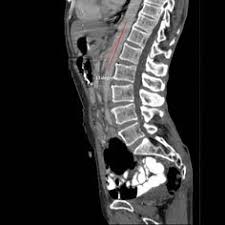

Superior Mesenteric Artery Syndrome Radiology Case Radiopaedia Org

Acute Gastric Dilation Caused By Superior Mesenteric Artery Syndrome Postgraduate Medical Journal

Significant Gastric Distension Caused By Superior Mesenteric Artery Syndrome Or Wilkie S Syndrome Gastroenterologia Y Hepatologia English Edition